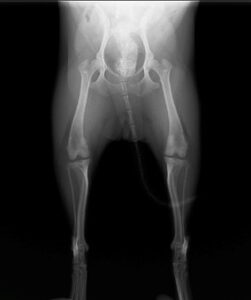

眼球摘出、眼瞼腫瘤切除、チェリーアイ整復、眼瞼縫合、瞬膜フラップ、眼球突出整復、耳介切除、垂直耳道切除、総耳道切除、鼻鏡切除、口腔腫瘍切除(上顎骨切除、下顎骨切除を含む)、各種抜歯(猫の全臼歯抜歯含む)舌腫瘍切除、唾液腺嚢胞切除、皮膚腫瘤切除、断脚(前肢、後肢、片側骨盤切除)、断尾、肺葉切除、胸腺腫切除、心膜切除、横隔膜ヘルニア整復、肝臓腫瘍切除、胆嚢摘出、胃切開、胃拡張胃捻転症候群整復、胃腫瘍切除、腸管切開、腸管腫瘍切除、直腸腫瘍切除(粘膜、全層プルスルーなど)、腎臓摘出、SUB設置手術、脾臓摘出、副腎摘出、膀胱切開、膀胱腫瘍切除(部分切除、全摘出、膀胱尿道一括切除など)、卵巣腫瘍切除、精巣腫瘍切除、卵巣子宮全摘出、肛門嚢切除、各種骨折、膝蓋骨脱臼整復、股関節脱臼整復、大腿骨頭切除、椎間板ヘルニア(各種椎弓切除術)、各種リンパ節切除 など